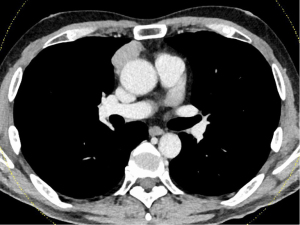

A male in his 50s visited a local hospital for fever and taste disorder, especially for the loss of sweet taste. He expressed his experiences as “I feel chocolate tastes like sand.” Chest computed tomography (CT) revealed an anterior mediastinal mass measuring 10 cm in maximal diameter (Figure 1). He was referred to Nagoya University Hospital for further examination and treatment. A CT-guided percutaneous transthoracic needle biopsy showed type B3 thymoma. Moreover, the 18F-fluorodeoxyglucose (FDG) positron emission tomography (PET)-CT scan showed high accumulation in mediastinal mass [the maximum standardized uptake-value (SUVmax): 5.89]. The clinical stage was Masaoka stage III because of the suspected invasion of the left upper lobe (LUL). No subjective symptoms were observed despite the elevated serum concentration of anti-acetylcholine receptor antibody (AchR-Ab) (6.1 nmol/L, normal range: <0.3 nmol/L). The level of plasma albumin before surgery was within the normal limit. He was on no medications before the surgery. In 2014 (before the COVID-19 pandemic), an extended thymectomy combined resection with LUL, left phrenic nerve, and left brachiocephalic vein was performed via median sternotomy and left thoracotomy (at fourth intercostal space). Pathological examination confirmed Masaoka stage II type B3 thymoma. The postoperative course was uneventful, and the patient was discharged from our hospital on postoperative day 8. There was no improvement in taste disorder after surgical resection of the thymoma. Forty-four days after surgery, the patient visited the emergency unit for dysphagia and shortness of breath. The patient was diagnosed with MG crisis and underwent intensive treatment with mechanical ventilation, steroid pulse therapy [methylprednisolone (mPSL), 1,000 mg/day/body for 3 days], and intravenous immunoglobulin (IVIG) therapy (20 g/day/body for 3 days). The patient regained taste when he started oral food intake after the treatment for a MG crisis (about 3 months after surgery). Despite the recovery of taste after steroid pulse therapy and IVIG therapy, taste disorder gradually worsened about 1 year and 9 months after surgery, resulting in an almost complete loss of sweet taste 2 years after surgery. The patient is alive without recurrence of thymoma, 7 years after surgery, without the recovery of taste.